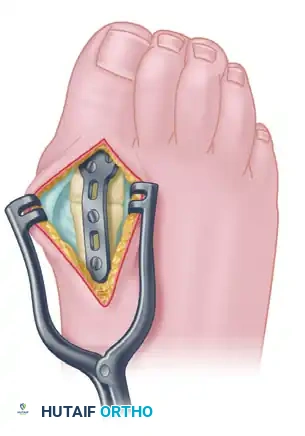

5. Definitive Internal Fixation

The method of internal fixation depends on surgeon preference, but the biomechanical gold standard is an obliquely placed headless compression screw combined with a precontoured dorsal neutralization plate.

Place the interfragmentary compression screw from distal-medial to proximal-lateral, ensuring it crosses the arthrodesis site and engages the thick lateral cortex of the metatarsal diaphysis. Predrill the near cortex before placement. Completely countersink the head of the screw into the proximal phalanx to prevent soft-tissue irritation.

Once interfragmentary compression is achieved, secure the precontoured, low-profile fusion plate to the dorsal aspect of the MTP joint using 2.7-mm to 4.0-mm multi-use compression or locking screws. In patients with osteopenia or poor bone quality, utilize larger screw sizes or locking technology to gain additional purchase and prevent hardware pullout.

3. First MTP Arthrodesis via Medial Approach

Excise the articular cartilage and subchondral bone of the metatarsal head and the base of the proximal phalanx using an osteotome or oscillating saw. The cuts must be angled precisely to place the arthrodesis in 10 to 15 degrees of valgus and 15 to 20 degrees of dorsiflexion.

Proceed with internal fixation of the first MTP joint using the lag screw and dorsal plate construct described in Technique 84-2. For the lesser toes, fixed hammer toe deformities are corrected by resecting 30% to 40% of the distal aspect of the proximal phalanx (the phalangeal bases are intentionally preserved to maintain soft tissue tension).